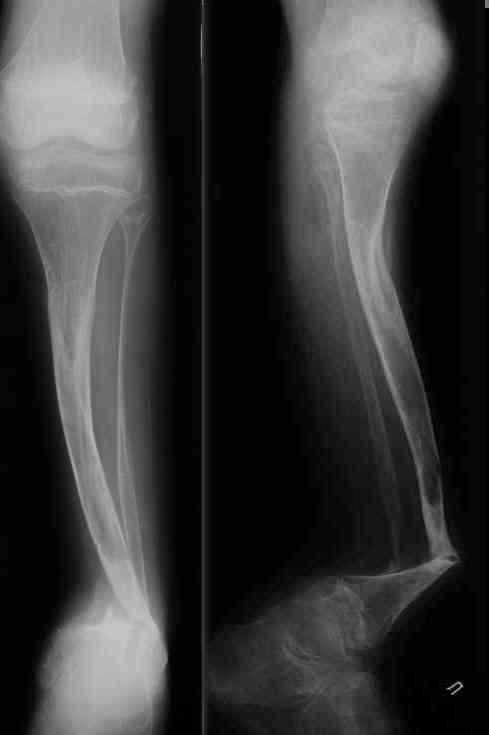

Уважаемые коллеги! В отделении на лечении наблюдается пациент 16 лет с диагнозом: Псевдоартроз костей левой голенив нижней трети. Вальгусная деформация обоих коленных суставов. Укорочение левой н/конечности11см. С 1997 года состоит на учёте у онколога с диагнозом: Рабдомиосаркома мышц тазового дна IV ст., с метастазами в метафизы берцовых костей.Проведена полихимиотерапия, лучевая терапия. В 1998 г. удаление опухоли. Послеоперационный период без особенностей. С 1998 года со стороны онкологии ремиссия, перестройка очагов метастазирования в берцовых костях по типу фиброзной дисплазии.В 1999 г. патологический перелом костей левой голени в н/трети. Лечение в гипсе 1.5 месяца, затем компрессионно-дистракционный остеосинтез апп. Илизарова. Сращения на месте псевдоартроза не достигнуто. С 1999г. ходит без нагрузки на левую н/конечность. Выраженный остеопороз костей н/конечностей. 17.11.05. Операция: Костная пластика зоны псевдоартроза левой б/берцовой кости по типу "русский замок", остеосинтез пластинкой и винтами. После начала нагрузки на конечность рецидив деформации, миграция фиксаторов. 05.12.06. Операция: Удаление фиксаторов из левой голени. Шарнирная остеотомия трети левой б/берцовой кости, остеотомия м/берцовой кости. Дистракционный остеосинтез апп. Илизарова. Устранены основные виды деформации б/берцовой кости. Планировали в дальнейшем несвободную костную аутопластику и интрамедуллярный остеосинтез с блокированием, но кость очень тонкая, склерозированная, выраженный остеопороз. Возникают большие сомнения о возможности сращения даже при этих условиях. Будем рады услышать ваши мнения по дальнейшему лечению данного пациента. Екатериан Анатольевна Озерова, детское отделение УНИИТО